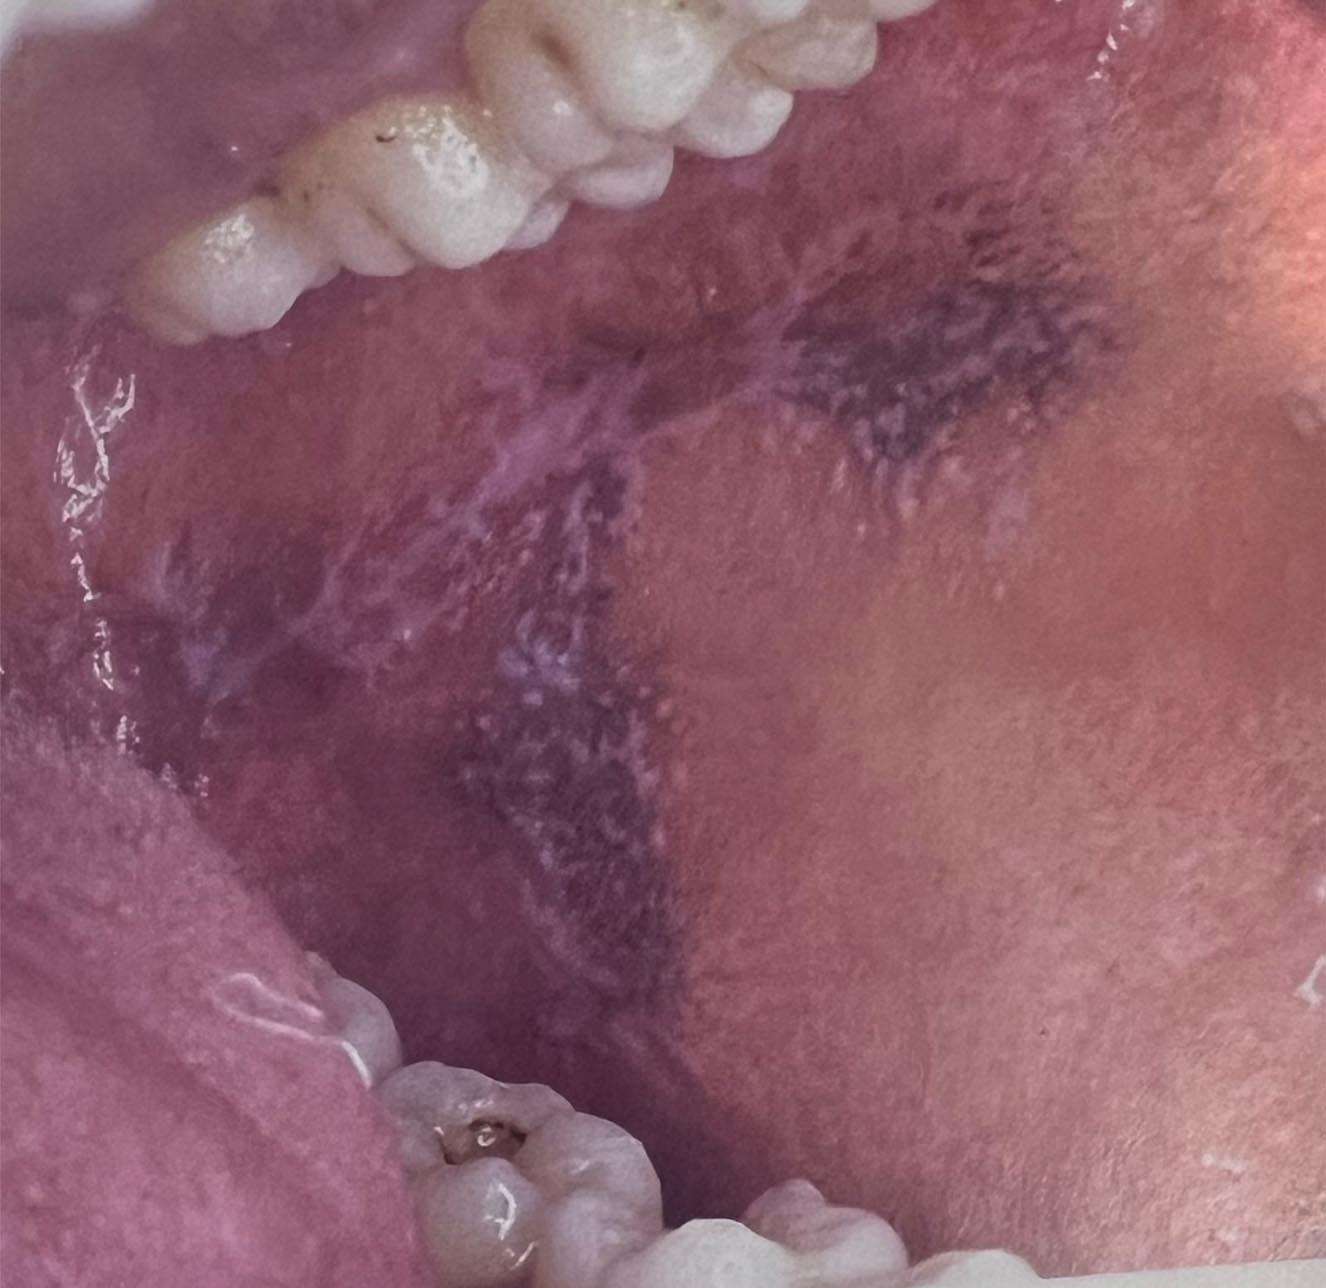

ಲೈಕನ್ ಪ್ಲ್ಯಾನಸ್ ಎಂಬುದು ಕ್ಯಾನ್ಸರ್ ಪೂರ್ವ ಸ್ಥಿತಿಯಾಗಿದ್ದು ಯಾವುದೇ ನಿರ್ದಿಷ್ಠ ಕಾರಣಗಳು ಇಲ್ಲದೆ ಬರುವ ರೋಗವಾಗಿರುತ್ತದೆ. ಈ ಕ್ಯಾನ್ಸರ್ ಪೂರ್ವ ಸ್ಥಿತಿ ಚರ್ಮದಲ್ಲಿ ಮತ್ತು ಬಾಯಿ ಕುಹರದ ಒಳಭಾಗದ ಪದರಗಳಲ್ಲಿ ಕಂಡು ಬರುತ್ತವೆ. ಬಾಯಿಯೊಳಗೆ ಬಿಳಿ, ಕೆಂಪು, ಮಚ್ಚೆಗಳಂತೆ, ಬಲೆಗಳಂತೆ ಕಂಡು ಬರುವ ಅಪಾಯ ರಹಿತ ಕ್ಯಾನ್ಸರ್ ಅಲ್ಲದ ರೋಗ ಇದಾಗಿರುತ್ತ್ತದೆ. ಬಾಯಿಯೊಳಗೆ ಈ ರೀತಿ ಬರುವಾಗ ಅದನ್ನು ಓರಲ್ ಲೈಕನ್ ಪ್ಲ್ಯಾನಸ್ ಎಂದು ಕರೆಯಲಾಗುತ್ತದೆ. ಇದು ಸೋಂಕು ರೋಗವೂ ಅಲ್ಲ ಮತ್ತು ಇನ್ನೊಬ್ಬರಿಗೆ ಹರಡುವ ಸಾದ್ಯತೆ ಇರುವುದಿಲ್ಲ. ಯಾವುದೇ ನಿರ್ದಿಷ್ಟ ನಿಖರ ಕಾರಣಗಳು ಇಲ್ಲದೆ ಈ ರೋಗ ಬರುತ್ತದೆ. ನಮ್ಮ ದೇಹದ ಪ್ರತಿರೋದಕ ಶಕ್ತಿ ಕುಗ್ಗಿದಾಗ ಈ ರೋಗ ಬರುವ ಸಾದ್ಯತೆ ಹೆಚ್ಚಾಗಿರುತ್ತದೆ. ನಮ್ಮ ದೇಹದ ರಕ್ಷಣಾ ವ್ಯವಸ್ಥೆಯಲ್ಲಿ ಉಂಟಾಗುವ ಸಂಕೀರ್ಣ ಪ್ರಕ್ರಿಯೆಗಳಿಂದ ಪ್ರತಿರೋಧಕ ಶಕ್ತಿ ಕುಗ್ಗಿ ಹೋಗಿ ಈ ಕ್ಯಾನ್ಸರ್ ಪೂರ್ವ ಸ್ಥಿತಿ ಬರುವ ಸಾದ್ಯತೆ ಇದೆ ಎಂದು ರೋಗ ರಚನಾ ಶಾಸ್ತ್ರದ ವೈದ್ಯರು ಅಭಿಪ್ರಾಯ ಪಟ್ಟಿದ್ದಾರೆ.

40 ವರ್ಷ ದಾಟಿದ ಬಳಿಕ ಈ ರೋಗ ಬರುವ ಸಾದ್ಯತೆ ಹೆಚ್ಚಾಗಿರುತ್ತದೆ. ಮಕ್ಕಳಲ್ಲಿ ಈ ರೋಗ ಬರುವ ಸಾದ್ಯತೆ ಅತ್ಯಂತ ವಿರಳ. ಪುರುಷರಿಗಿಂತ ಮಹಿಳೆಯರಿಗೆ ಈ ರೋಗ ಬರುವ ಸಾದ್ಯತೆ ಹೆಚ್ಚಾಗಿರುತ್ತದೆ. ಹೆಚ್ಚಾಗಿ ಕೆನ್ನೆಯ ಒಳ ಭಾಗ, ನಾಲಗೆಯ ಬದಿಯಲ್ಲಿ ಮತ್ತು ವಸಡುಗಳಲ್ಲಿ ಲೈಕನ್ ಪ್ಲ್ಯಾನಸ್ ಕಂಡು ಬರುತ್ತದೆ. ಹೆಚ್ಚಾಗಿ ಈ ರೋಗ ಮಚ್ಚೆಯ ಪರಿಧಿಯೊಳಗೆ ಹರಡಿದ ಬಿಳಿಯ ಗೆರೆಗಳುಳ್ಳ ಬಿಳಿಯ ಮಚ್ಚೆಗಳ ರೀತಿಯಲ್ಲಿ ಕಂಡು ಬರುತ್ತದೆ. ಕೆಲವೊಮ್ಮೆ ಹೊಲಿದ ಲೇಸ್ನಂತೆ ಅಥವಾ ಸೊಳ್ಳೆ ಪರದೆಯ ಲೇಸ್ನಂತೆ ವಿಶಿಷ್ಟ ವಿನ್ಯಾಸವಿರಲೂಬಹುದು. ಅತಿ ವಿರಳ ಸಂದರ್ಭಗಳಲ್ಲಿ ಕೆಂಪು ಬಣ್ಣ ಹೊಂದಿರಬಹುದು. ಇನ್ನು ಕೆಲವೊಮ್ಮೆ ಈ ಬಿಳಿ ಮಚ್ಚೆಗಳ ನಡುವೆ ಹುಣ್ಣು ಇರುವ ಸಾಧ್ಯತೆ ಇರುತ್ತದೆ.